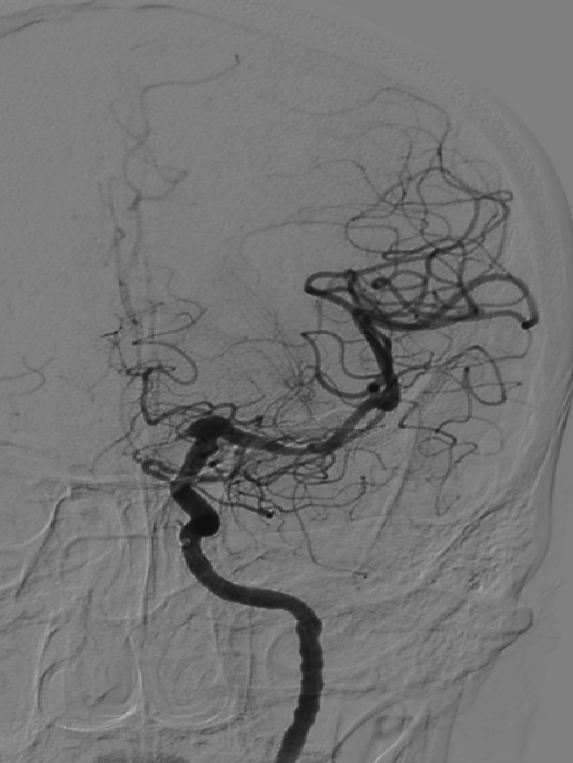

术前造影

造影显示:左侧A1段血流纤细,左侧前循环供血通过右侧A1段及前交通代偿。

左侧颈内动脉末端梭形夹层动脉瘤,2.9mm*3.5mm。